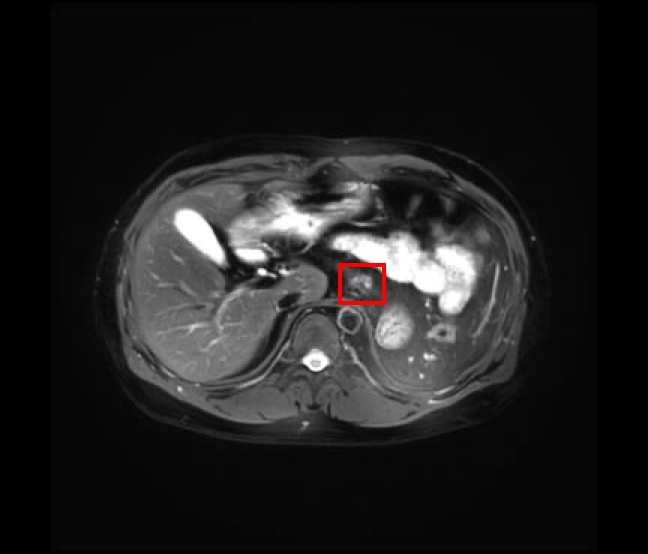

2025年4月,张先生接受了第一次疫苗注射,因彼时身体虚弱,并未出现预期的发热反应,这让他满心焦虑:“是不是药效不好?” 作为他的专属负责医生,内分泌代谢病学科武鲁铭医生第一时间耐心安抚:“每个人的身体反应不同,我们会持续监测各项指标,及时调整方案。” 此后,张先生每三周注射一次,期间但凡有血液指标等疑问,微信咨询武医生总能得到快速回复,这位专属的 “家庭医生”,让他倍感安心。原计划九周期的治疗,因肿瘤持续缩小得以延续,完成16次注射后,他的靶病灶明显缩小,全身无新发病灶,ACTH、皮质醇等激素水平经替代治疗趋于稳定。这场创新治疗,为肾上腺皮质癌的精准治疗开辟了新路径,也让张先生重燃生活希望,他坦言:“每次打针都是一次胜利,能陪着孩子慢慢长大,就是我最大的心愿。”

治疗前、疫苗前/后 影像图